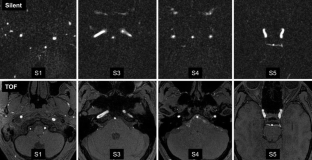

Fig. 3